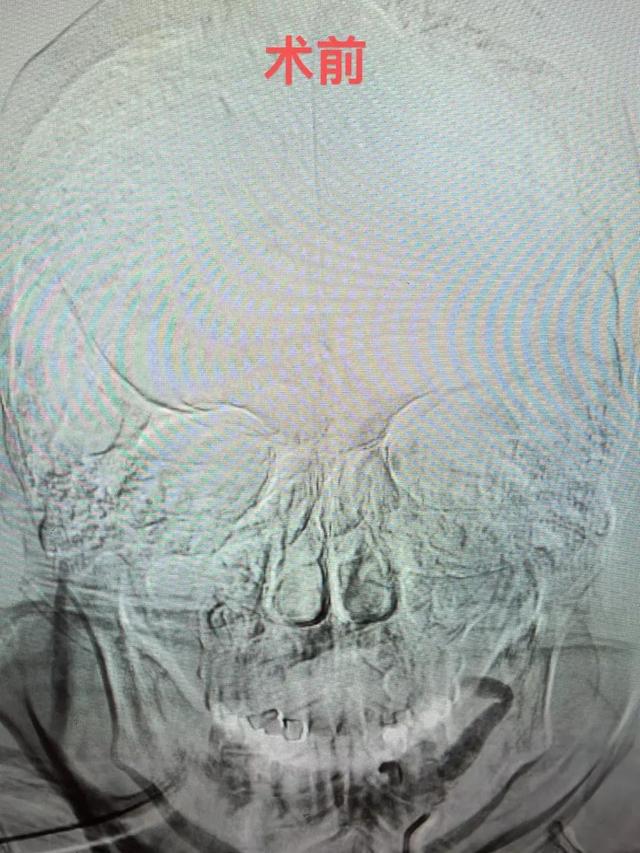

急诊医学科立即启动急救绿色通道,一方面进行脑卒中“一站式”CT检查【包括CT平扫、CT血管成像(CTA)和CT灌注成像(CTP)】,在3-5分钟内就完成脑卒中治疗前评估,为患者争取宝贵的时间。另一方面启动神经内科急会诊。

神经介入团队梁达主治医师接到会诊立即到达。他通过查体、综合石奶奶的症状和检查结果,诊断为:大面积脑梗死,左侧颈内动脉、大脑中、前动脉闭塞 、心房颤动、肋骨骨折,病情复杂而危重,考虑存在血栓脱落致急性脑动脉闭塞、静脉溶栓出血等风险,建议急诊直接介入取栓,有生的希望! 缪桂华副主任医师带领团队成员研究制定了手术和麻醉方案。虽然高龄,石奶奶耳聪目明,她的家属都表示非常希望能够尽快手术来挽救生命。